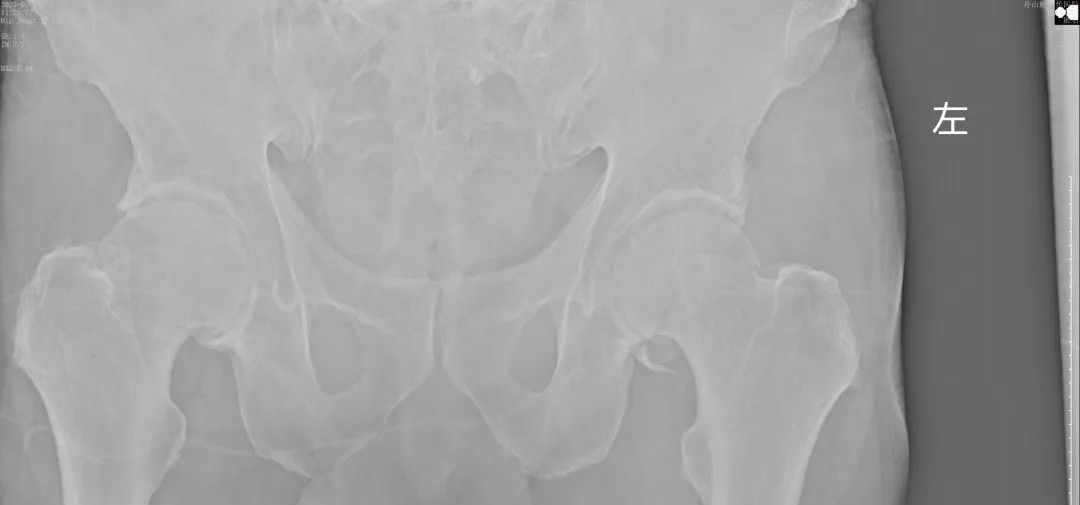

經(jīng)過王副主任認(rèn)真仔細(xì)的檢查,并結(jié)合X線攝片后,他告訴患者及其家屬:“周大爺是外傷導(dǎo)致的急性髖關(guān)節(jié)脫位、髖臼骨折!”一聽脫位骨折了,患者及家屬焦慮萬分,擔(dān)心手術(shù)給身體和經(jīng)濟(jì)帶來的巨大壓力。王副主任耐心告知周大爺一家人:“周大爺這種病情可以保守治療,用我們顧氏的正骨手法可以復(fù)位的,不需要開刀,價格也實(shí)惠”。家屬聽到不用做手術(shù),瞬間放心不少,表示非常愿意配合治療。

(術(shù)后復(fù)片  關(guān)節(jié)對位良好)